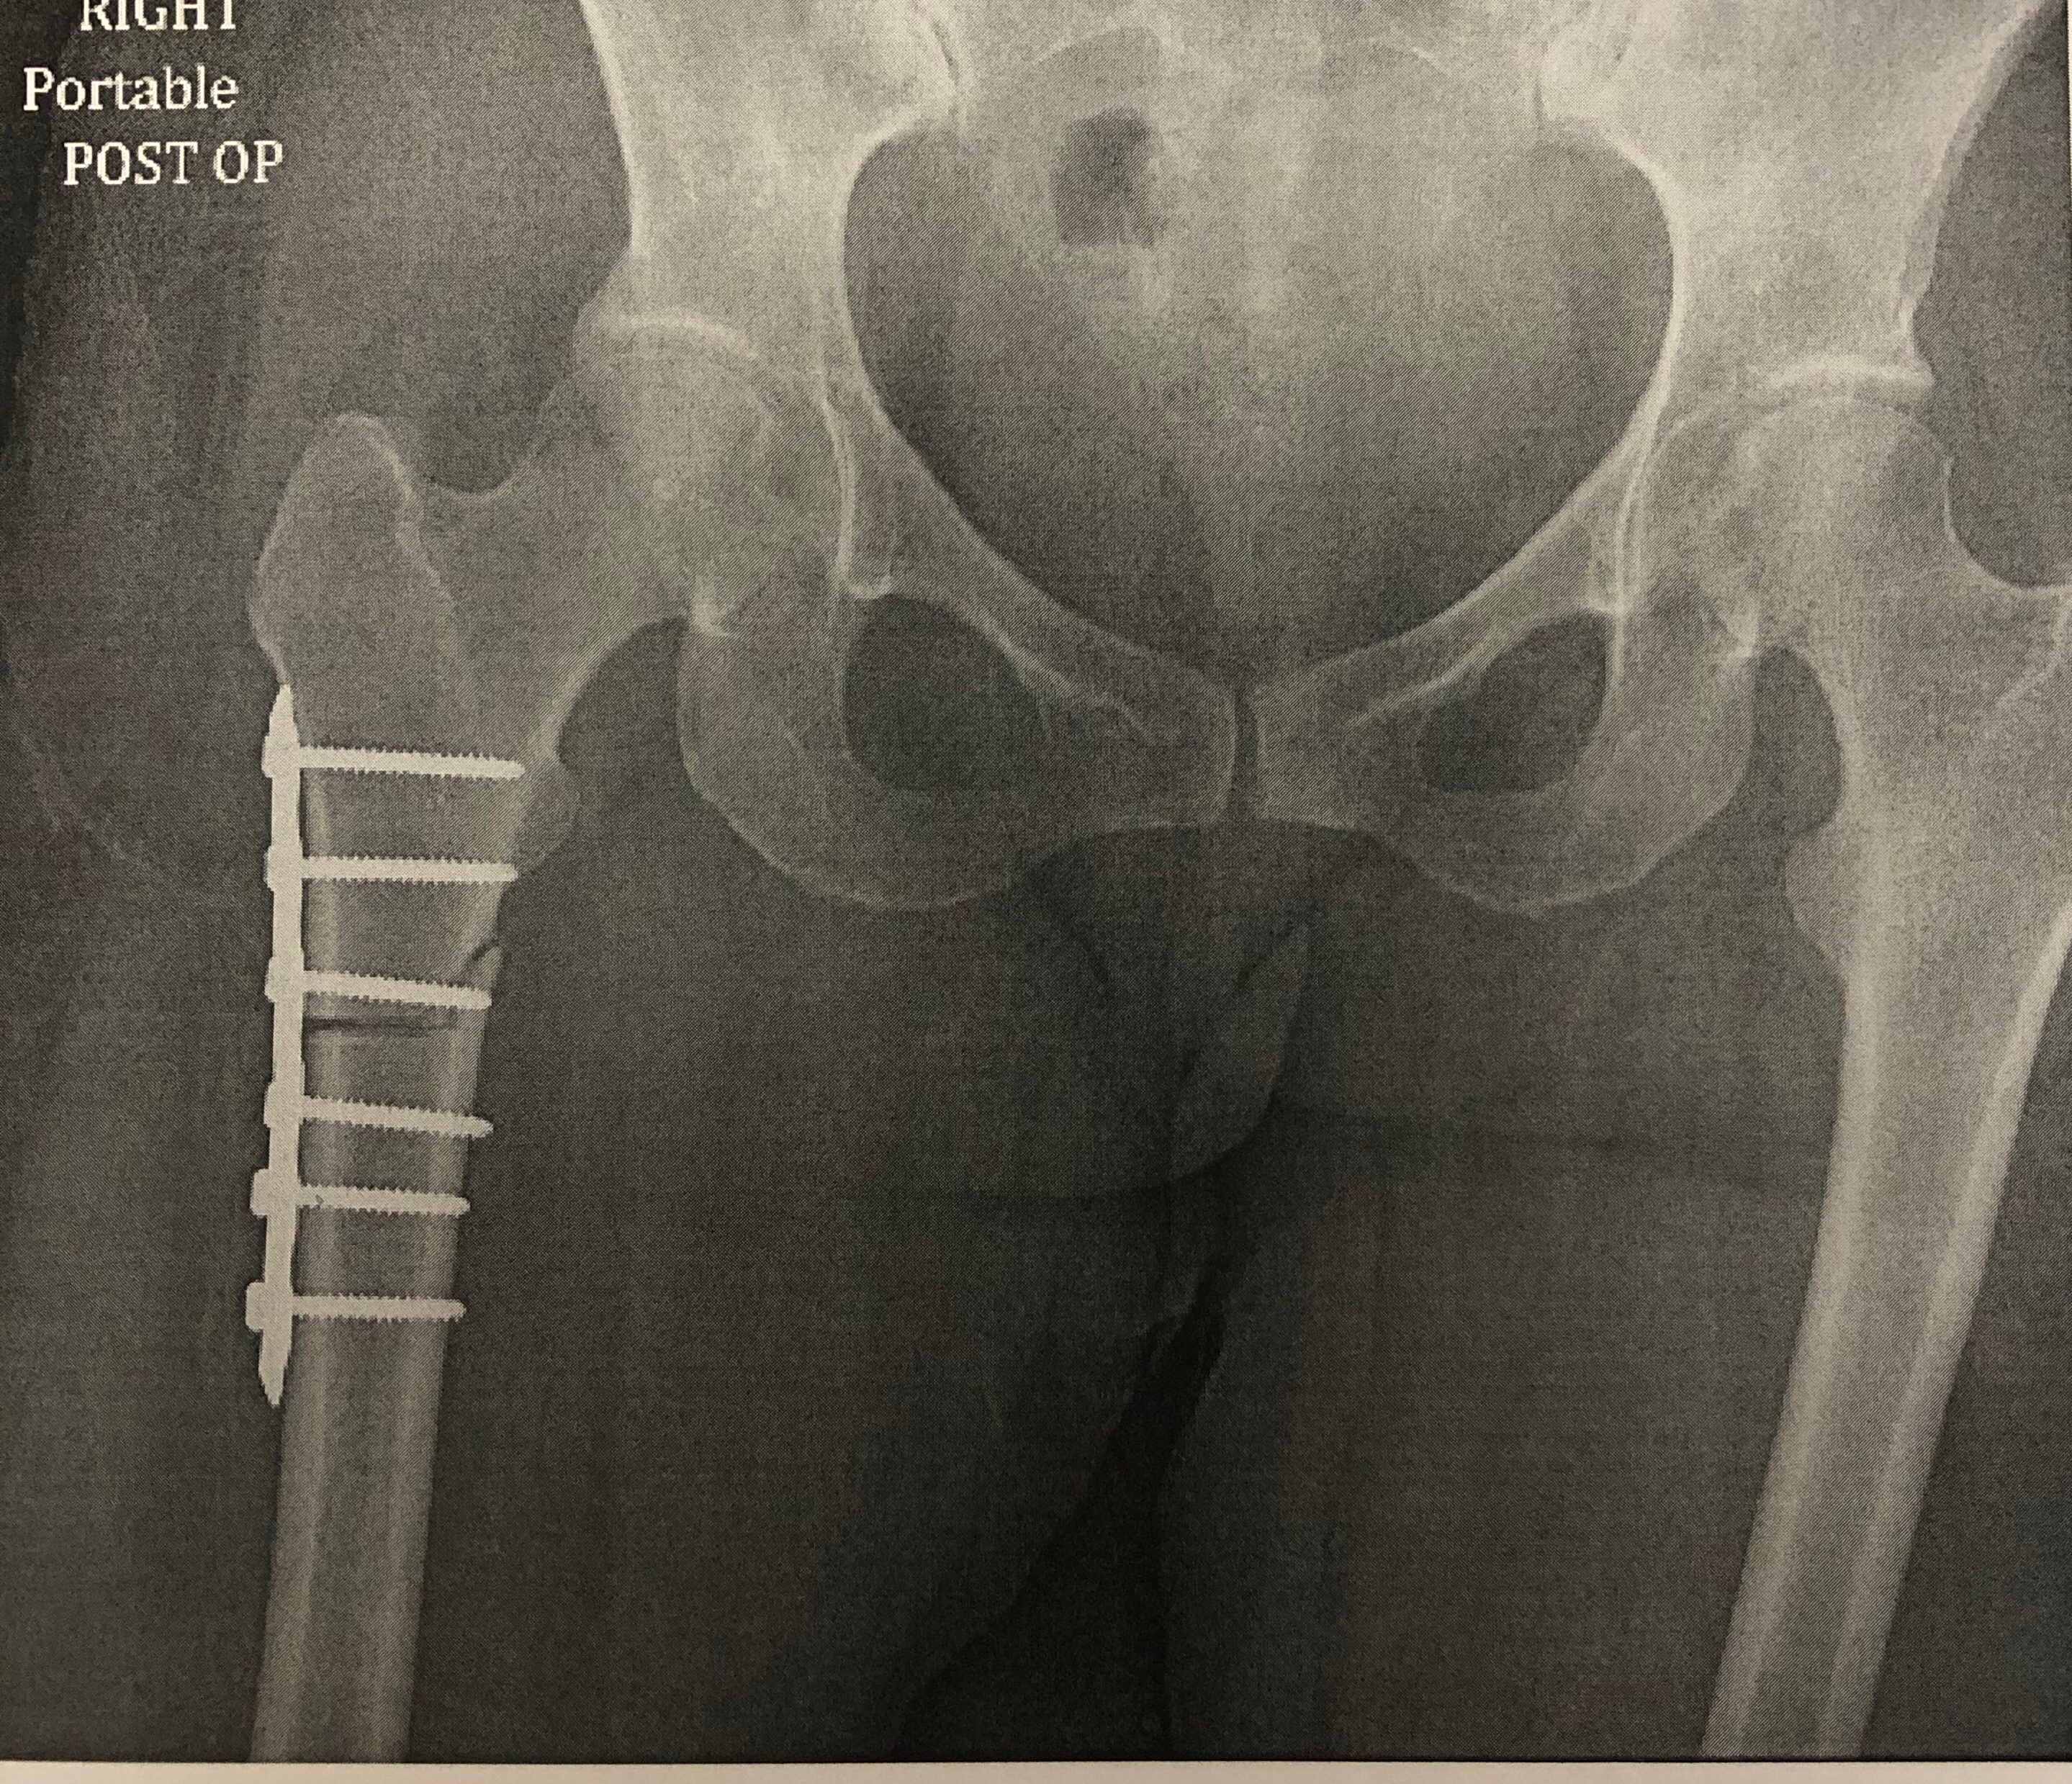

The only fix for femoral version issues is to perform a femoral osteotomy, which involves cutting the femur in half, rotating it and using hardware to put it back together. In my case, the surgeon used a metal plate and six screws. This surgery readjusts the position of the femoral head and ensures it fits well within the acetabulum. Although only the bone was cut, it affected the placement of all my muscles, tendons, ligaments and other soft tissues. He also had to manually move my acetabulum up a bit to have the femur fit correctly.